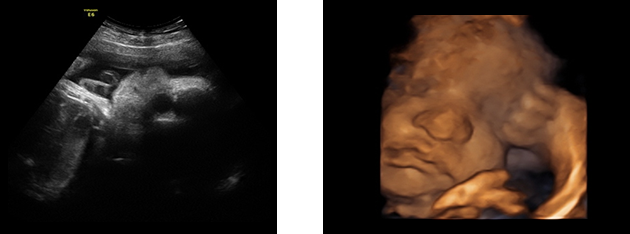

3d 4d超音波外来 六本木一丁目駅直結の丸茂レディースクリニック 産科 婦人科 4d 3dエコー検査

3d 4dエコー 高輪台レディースクリニック 港区の産科 婦人科

4d画像 広尾 まきレディスクリニック